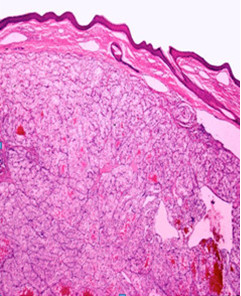

Volver a los detalles del artículo Metástasis cutáneas por un adenocarcinoma renal